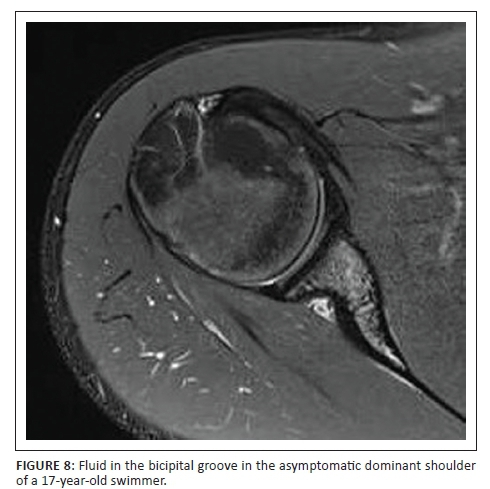

Of the asymptomatic shoulders studied, 86.2% had MRI changes which could be viewed as abnormal. This corresponds to previous studies that showed that MRI abnormalities in asymptomatic overhead athletes are common.2,4,11 The most common findings in both the symptomatic and asymptomatic shoulders were subacromial subdeltoid fluid (Figure 5), increased signal at the AC joint (Figure 6), AC joint arthrosis, supraspinatus tendinosis (Figure 7) and biceps tendinosis (Figure 8). There were 11 symptomatic shoulders in our sample group with the most common clinical findings being impingement, AC joint tenderness, positive O' Brien's sign and biceps tenderness. The asymptomatic group also demonstrated positive clinical findings, with subacromial impingement, biceps tenderness and sternoclavicular tenderness being the most common findings. AC Joint tenderness was less common in the asymptomatic group. The studied group consisted of a slightly smaller symptomatic group than Sein et al., but our athletes more frequently demonstrated local AC joint tenderness and positive O'Brien's sign. Increased signal at the AC joint is a common finding in both the symptomatic and asymptomatic shoulders of overhead athletes and does not correlate with patient symptomatology as also noted in agreement with Reuter et al.12 In this study, type 1 acromion shape was most common followed by type 2 and type 3. There was no direct correlation between shoulder pain and acromion shape.

Supraspinatus tendinopathy was a common finding in both the symptomatic and asymptomatic shoulders, with it being nearly twice as common in the symptomatic shoulders. Previous studies also found supraspinatus tendinopathy to be a dominant finding.4 Biceps tendinosis was approximately twice as common in the symptomatic shoulder. Connor et al. showed that subacromial subdeltoid fluid was a common finding in the asymptomatic shoulder.6 This study demonstrated similar results with subacromial and/or subdeltoid fluid found in 34.5% of the asymptomatic shoulders. In a study where Reuter et al. evaluated shoulder MRI changes in 23 triathletes, 57% of the asymptomatic group and 31% of the symptomatic group demonstrated AC joint arthrosis.12 The current study demonstrated nearly equal percentages of AC joint arthrosis (36.4% symptomatic vs. 34.5% asymptomatic).